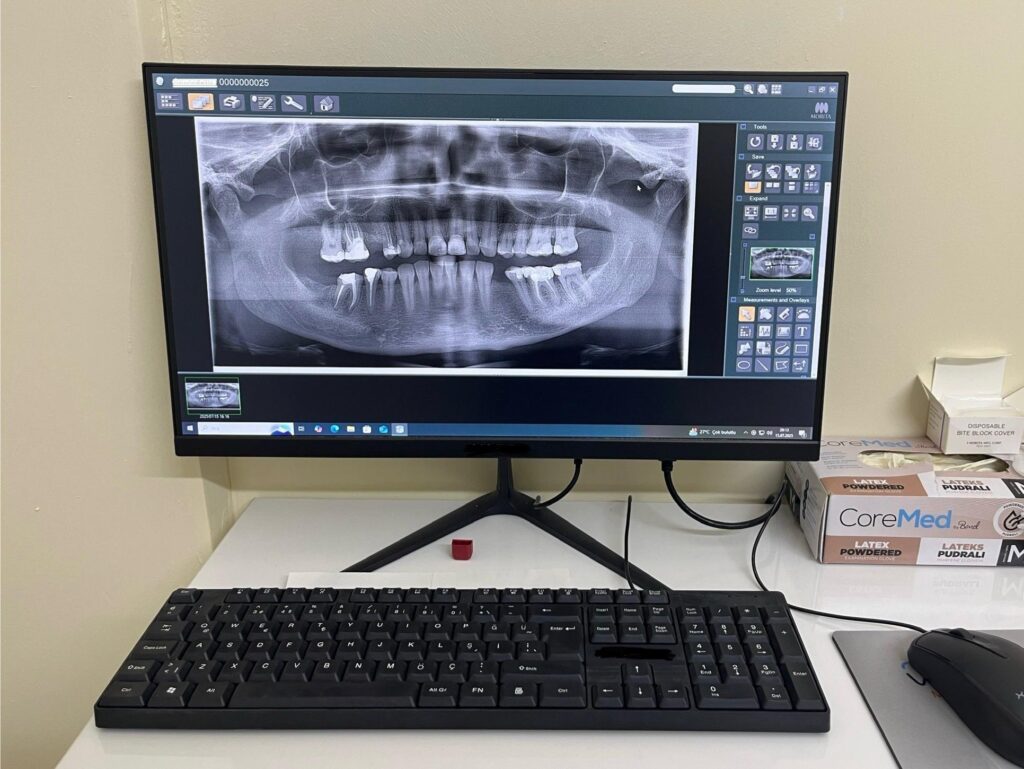

Bugün Antakya’da kurduğu muayenehanesinde; dijital diş hekimliğinin sunduğu en ileri teknolojilerle, estetik ve fonksiyonel tedavileri yüksek hassasiyetle uygulamakta, hastalarına konforlu, güvenilir ve modern bir tedavi deneyimi sunmaktadır.

Dijital diş hekimliği, implant tedavisi, estetik diş hekimliği ve gülüş tasarımı alanlarında en güncel teknolojileri kullanarak güvenilir çözümler üretiyoruz.